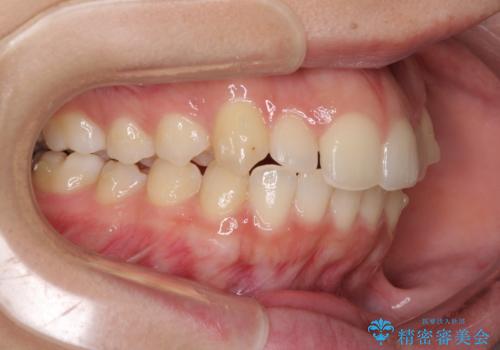

骨格的に左右にずれいている 前歯のデコボコをインビザラインで解消

- 前歯のデコボコと八重歯を気にして来院された患者様です。

叢生の程度は中等度であったため、IPR(歯と歯の間を削る)と歯列の側方拡大をメインに、インビザラインを用いて歯列を改善することとしました。

また、下顎骨の右側変位による右側臼歯の咬合を改善させるよう試みることとしました。

右側の咬合改善を目標に様々な手法を用いましたが、骨格的なズレによる不正咬合はインビザラインでは改善することができませんでした。